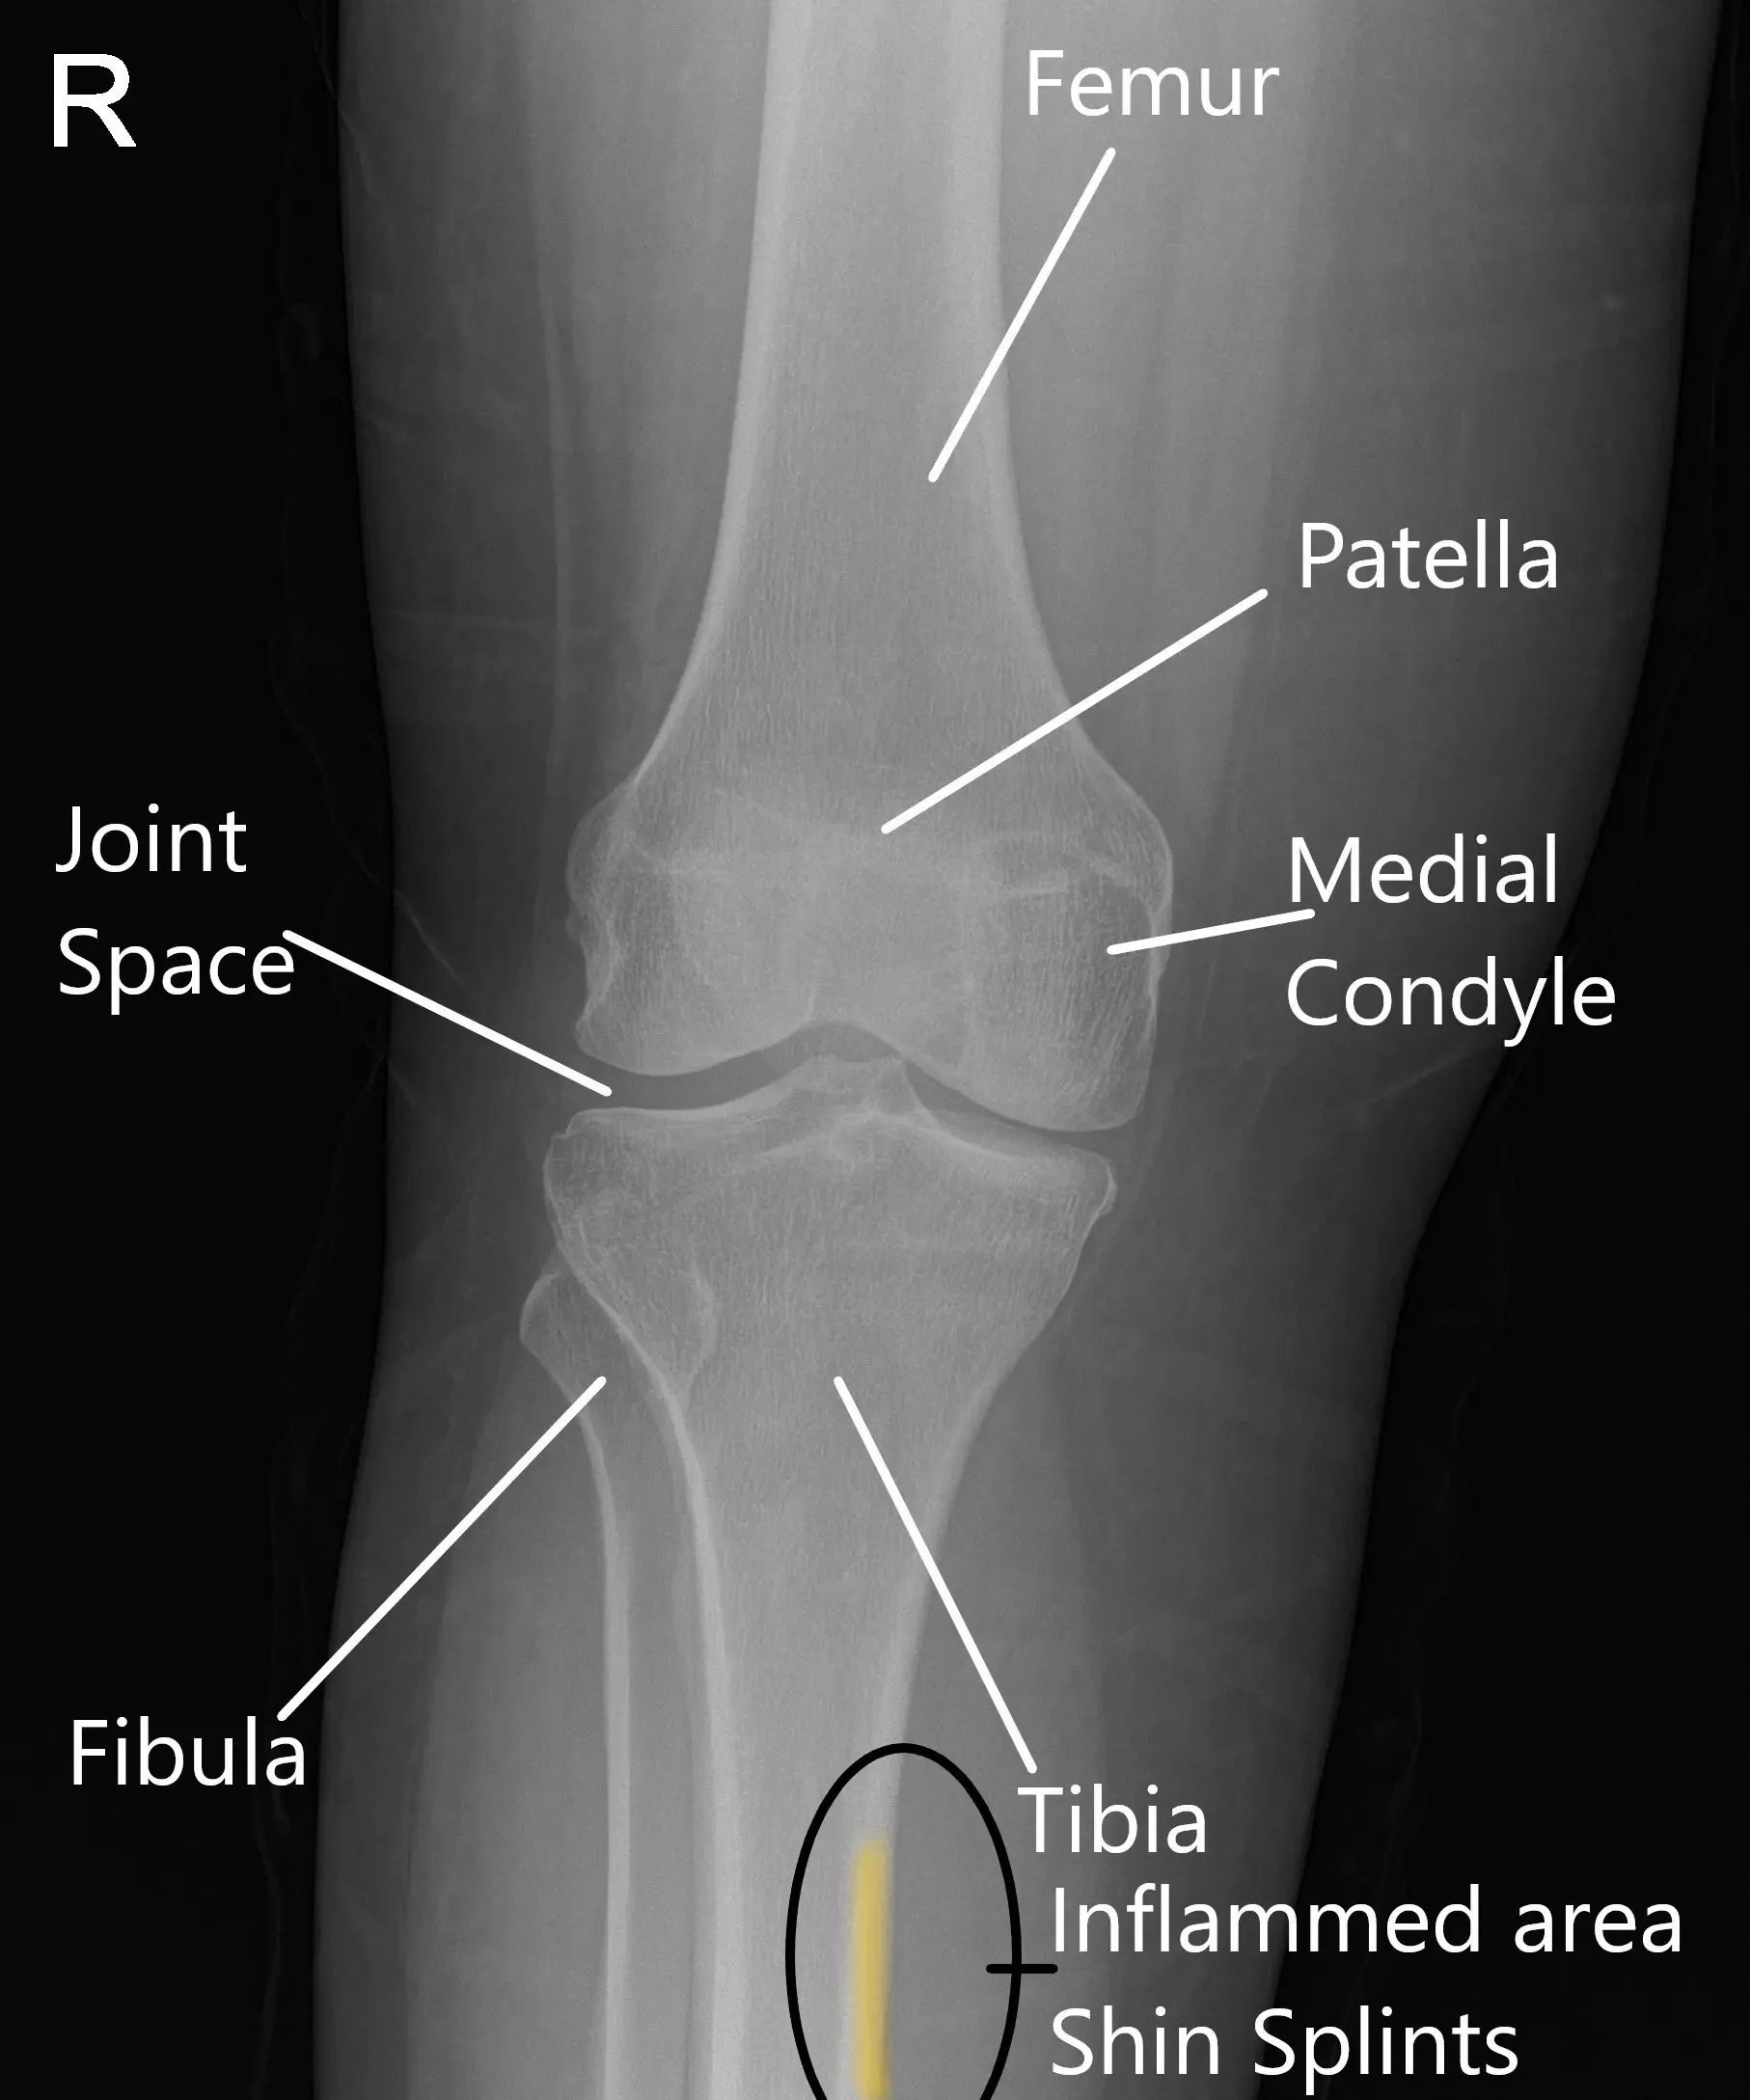

Radiografía de una rodilla normal que muestra la zona inflamada en la periostitis tibial.

La tibia, o espinilla, es el hueso largo de la pierna inferior. Está rodeado de músculos, tendones y el periostio. El periosteo ayuda a proteger y nutrir el hueso, mientras que músculos como los de la pantorrilla y el tibial anterior son responsables del movimiento. Durante actividades como correr o saltar, estos músculos se contraen y aplican fuerza a la espinilla. Si los músculos y tendones están sobrecargados, puede provocar inflamación y dolor a lo largo del borde interno de la tibia.